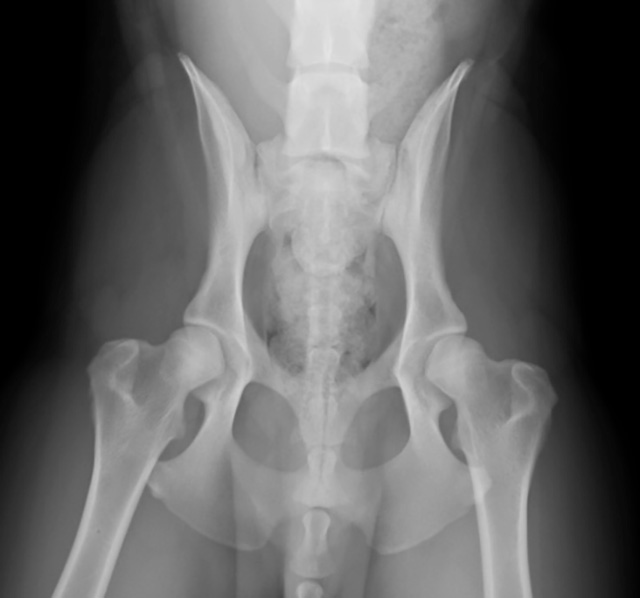

前十字靭帯は、膝が正常な位置にあるために必要な靭帯です。この前十字靭帯が、年齢や外傷など様々な原因で弱くなり切れてしまうのが、前十字靭帯断裂です。

この病気は、急に痛がった後、足をつかなくなるという症状が多いです。このような症状に対して、当院ではまずしっかり触診を行います。そして、膝のレントゲン検査も行い診断をします。治療は、内科治療から外科治療まで幅広い選択肢をご提示します。外科手術は、2次診療施設への紹介をさせていただきます。

「歩き方がおかしい」という異常であっても、筋肉や骨の病気(整形疾患)か、脳や神経の病気(脳神経疾患)か、ここを見分けることがとても大事になってきます。そしてここでとても重要なのが、触診(触る検査)です。二次診療施設での研修経験も生かし、丁寧に触診を行います。また骨などの異常を疑う場合は、高性能レントゲン装置でそれを確認し分かりやすく説明します。